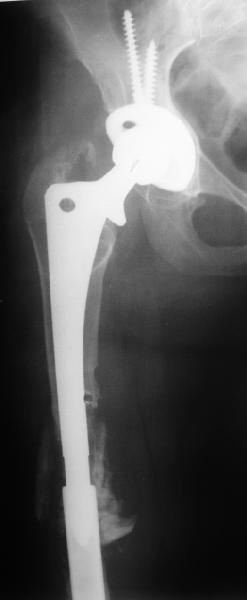

Female, rheumatoid, THA in 2003, car accident in 2006, failed plating. Nailing in Oct 2007. The nail is solid with hollow proximal part where the stem is docked. Last images are in 1 year after

nailing.

Спасибо за обсуждение. После нескольких дней тракции аппаратом сделали. Попытка закрытой репозиции не удалась из-за смещения по ширине, мешали фрагменты цемента. После их удаления репозиция получилась. Еще убрали немного цемента с ножки по латерльной стороне, чтобы обнажить 40-50 мм ее дистальной части, для плотной посадки гвоздя. Дальнейшее введение гвоздя было несложным. Протез показался нам стабильным в проксимальной части как латерально, так и медиально. Картинки в приложении.

THX for the discussion. After few days of traction by ex-fix the surgery was performed. An attempt of closed nailing was unsuccesful because of fragment translation, which was blocked by cement fragments. After removal of broken cement pieces reduction was reached "automagically". Also some cement from lateral part was removed by

chisel to expose distal 40-50 mm of the stem to allow tight fit of the nail. Further fixation by the nail was pretty easy and straightforward. Images attached. The stem looked stable in its proximal part both laterally and medially. Comments/critics are welcome.